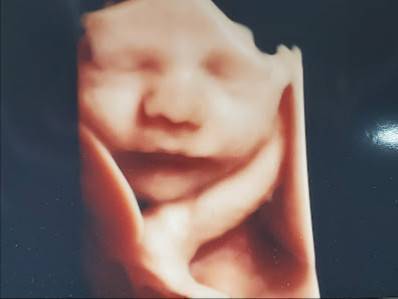

Enso Prenatal & 3D/4D Ultrasounds - Colorado Springs, Colorado

Specialties: Medical diagnostic imaging center, Childbirth class, Massage therapist, Yoga studio.

Enso Prenatal & 3D/4D Ultrasounds ofrece una variedad de servicios para satisfacer las necesidades de las mujeres en diferentes etapas de su vida. Desde la imagen médica diagnóstica hasta la clase de parto y el masaje, este centro ofrece un ambiente acogedor y profesional para que las mujeres se sientan cómodas y seguras.

Enso Prenatal & 3D/4D Ultrasounds tiene 179 opiniones en Google My Business, con una media de 5/5 estrellas. Los clientes elogian la atención personalizada, el equipo profesional y el ambiente acogedor del centro.